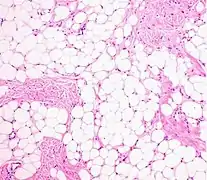

A lipoma is a benign tumor made of fat tissue.[1] They are generally soft to the touch, movable, and painless.[1] They usually occur just under the skin, but occasionally may be deeper.[1] Most are less than 5 cm (2.0 in) in size.[2] Common locations include upper back, shoulders, and abdomen.[4] It is possible to have a number of lipomas.[3]

• Superficial subcutaneous lipomas, the most common type of lipoma, lie just below the surface of the skin.[13] Most occur on the trunk, thigh, and forearm, although they may be found anywhere in the body where fat is located.[14]